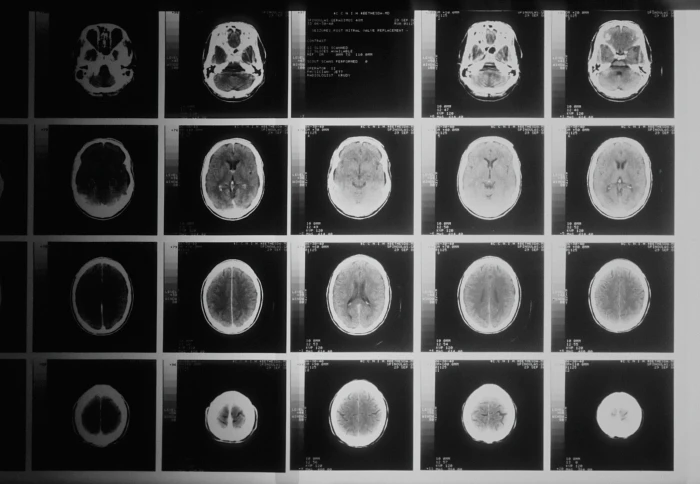

Diagnosing Alzheimer’s with a single brain scan

A ground-breaking study by Imperial found a single MRI scan of the brain could be enough to diagnose Alzheimer’s disease. The research used machine learning technology to look at structural features within the brain, including in regions not previously associated with Alzheimer’s.

The researchers found that in 98 per cent of cases, the MRI-based machine learning system alone could accurately predict whether the patient had Alzheimer’s disease or not. It was also able to distinguish between early and late-stage Alzheimer’s in 79 per cent of patients.

Professor Eric Aboagye, from Imperial’s Department of Surgery and Cancer, who led the research, said: "Currently no other simple and widely available methods can predict Alzheimer’s disease with this level of accuracy, so our research is an important step forward."